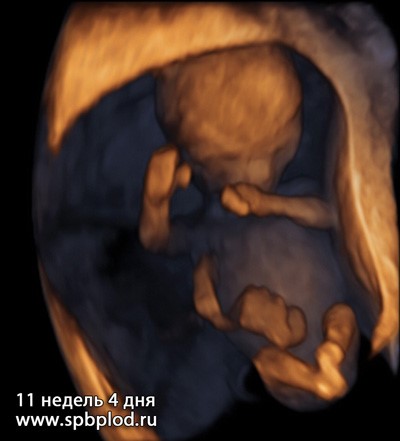

А так выглядит плод на объемных изображениях (3D/4D УЗИ) в первом триместре:

3D УЗИ пплода в 11 недель и 4 дня